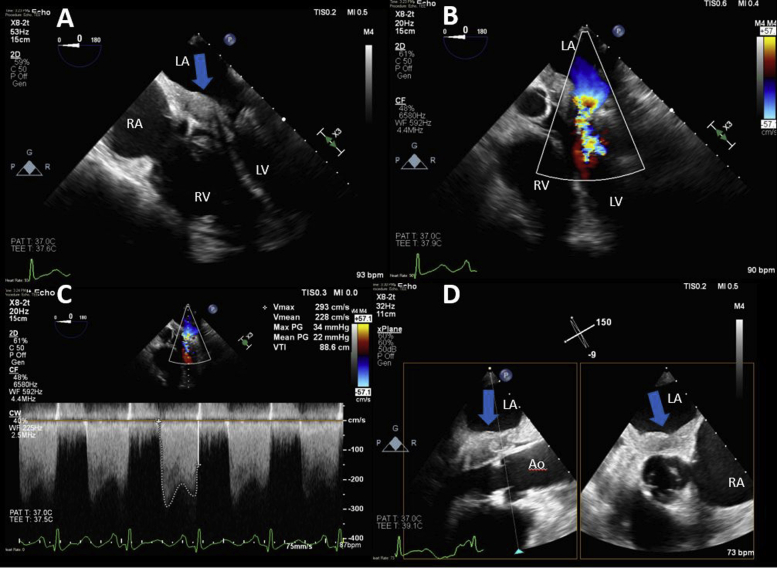

A transthoracic echocardiogram (TTE) performed in the office that demonstrated a layering, noncalcified mass in the left atrium involving the anterior mitral valve leaflet obstructing mitral inflow (Figure 1, Videos 1 and 2). There was associated severe mitral stenosis (mean gradient = 22 mm Hg best seen on transesophageal echocardiography [TEE]; Figure 2), severe mitral regurgitation (Figure 2, Video 3), and severe pulmonary hypertension (pulmonary artery systolic pressure = 95 mm Hg). The interventricular septum was D shaped in systole consistent with elevated right heart pressures, and a small posterior pericardial effusion was noted (Figure 1B, Video 4). The patient was referred for cardiac magnetic resonance imaging (CMR) to better characterize the abnormality. Cardiac magnetic resonance imaging demonstrated a mass arising along the septum and inferior wall of the left atrium extending down along the anterior mitral valve leaflet (Figure 3, Video 5). The mass was not independently mobile and appeared to infiltrate these structures, resulting in significant mixed mitral valve disease. It measured 3.3 × 1.9 cm in the four-chamber view (Figure 3, Video 5). The mass was isointense to the myocardium on T1-weighted imaging with and without fat suppression and mildly hyperintense on T2-weighted imaging with fat suppression (Figure 4). The mass was found to perfuse poorly on first pass perfusion (Video 6), but there was evidence of hyperenhancement on early gadolinium enhancement imaging. Marked homogeneous hyperenhancement was noted on late gadolinium enhancement imaging along with evidence of a small amount of layered thrombus overlying the mass (Figure 4). There was no evidence of tumor infiltration in the pulmonary veins or right heart. Collectively the CMR findings were highly suggestive of a malignant cardiac tumor. The differential diagnosis at this point included primary cardiac sarcoma, lymphoma, or metastatic tumor. No definitive extracardiac malignancy was identified on computed tomography (CT) of the chest, abdomen, and pelvis, increasing our suspicion for a primary cardiac neoplasm.

Figure 2.

TEE two-dimensional imaging was performed to further evaluate the left atrial mass and guide the biopsy. (A) Large layering left atrial mass (blue arrow) extending to the mitral valve. The mass was associated with severe flow obstruction across the mitral valve (B, C). (D) Biplane imaging demonstrates the proximity of the mass (blue arrows) to the aortic valve. LA, Left atrium; LV, left ventricle; RA, right atrium; RV, right ventricle.